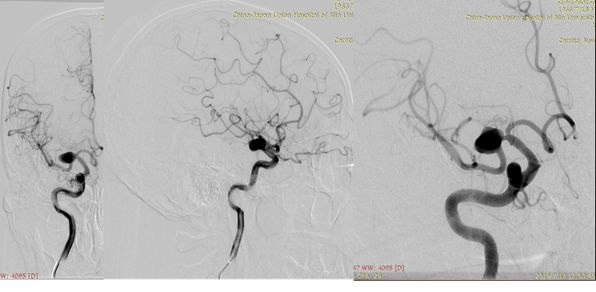

术前造影:

治疗颅内动脉瘤新型密网支架,pipeline治疗椎动脉夹层动脉瘤

1、造影后显示右侧大脑中动脉M1段动脉瘤,路径图引导下由Traxcess(0.014,200 cm)微导丝携带Marksman支架微导管超选进入右侧大脑中动脉M2段远端(图一)。

图一

2、Pipeline密网支架释放过程,图像显示支架打开及贴壁良好(图二)。

图二

3、术后支架显影(图三)。

图三

4、术后影像(图四)。

图四